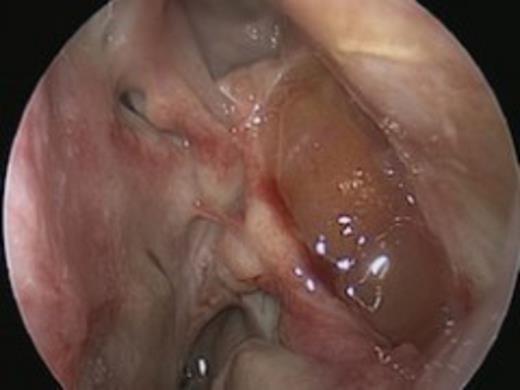

Fibreoptic nasendoscopy revealed a deviated nasal septum with significant oedema of the left middle turbinate with copious purulent secretions emanating from the left middle meatus. He was started on topical Fluticasone propionate nasules in addition to long-term antibiotics.

The radiological findings correlated with the clinical observations and the patient underwent Functional Endoscopic Sinus Surgery (FESS) to drain the large septic collection in the left maxillary antrum.

The operative findings included significant septic secretions within the left middle meatus and gelatinous soft tissue within the left maxillary antrum, which was sent for histological analysis. The infection was managed with appropriate antibiotics according to sensitivities, in addition to steroid nasules.

There was evidence of possible recurrence along the posterior and lateral wall of the maxillary sinus at routine follow-up. Hence, the patient underwent a revision left FESS and canine fossa puncture. Examination under anaesthesia was performed with 0, 45, and 70 degrees scopes respectively. This revealed recurrence in the posterior wall of the maxillary antrum, which was debrided to a shell of bone. Passage of the 70 degree scope through the canine fossa puncture demonstrated a further mass of abnormal mucosa which was completely debrided along the floor of the orbit. There were no postoperative complications, and follow-up was arranged for a month thereafter.